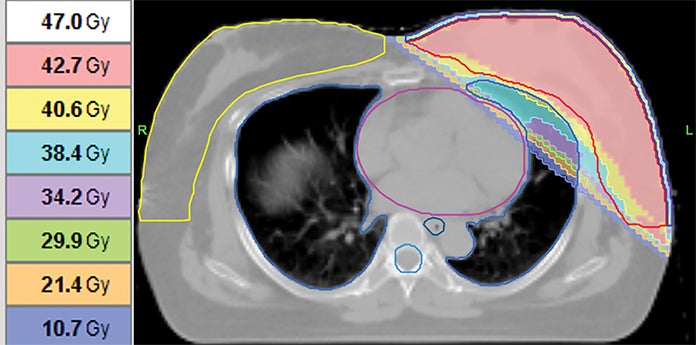

Case Report: Mediastinal Epithelioid Hemangioendothelioma in a Patient With Concurrent Early Stage Right Breast Cancer 💗🔗 ow.ly/88Kj50X8URp #BCAM25 #BreastCancerAwarenessMonth #WomensHealth #RadOncEd #MedEd